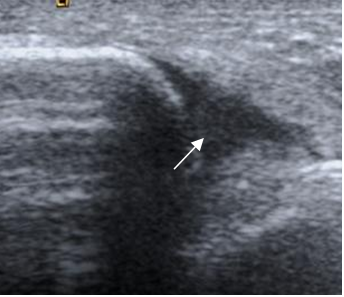

Fig 64 A. Lesión ligamentaria.

Ecografía longitudinal. Presencia de líquido y ausencia del ligamento peroneoastragalino anterior, por ruptura.